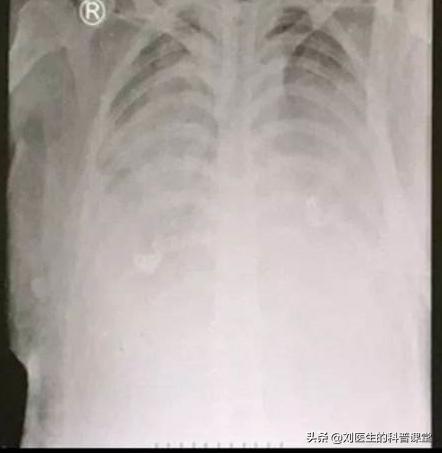

重症肺炎:白肺

对于“白肺”的患者,临床上治疗起来比较棘手,患者死亡率极高,近日武汉大学中南医院宣布通过"人工肺"成功救治一名重症患者,成为湖北首例,那么这个秘密*器武**"人工肺"是什么呢?